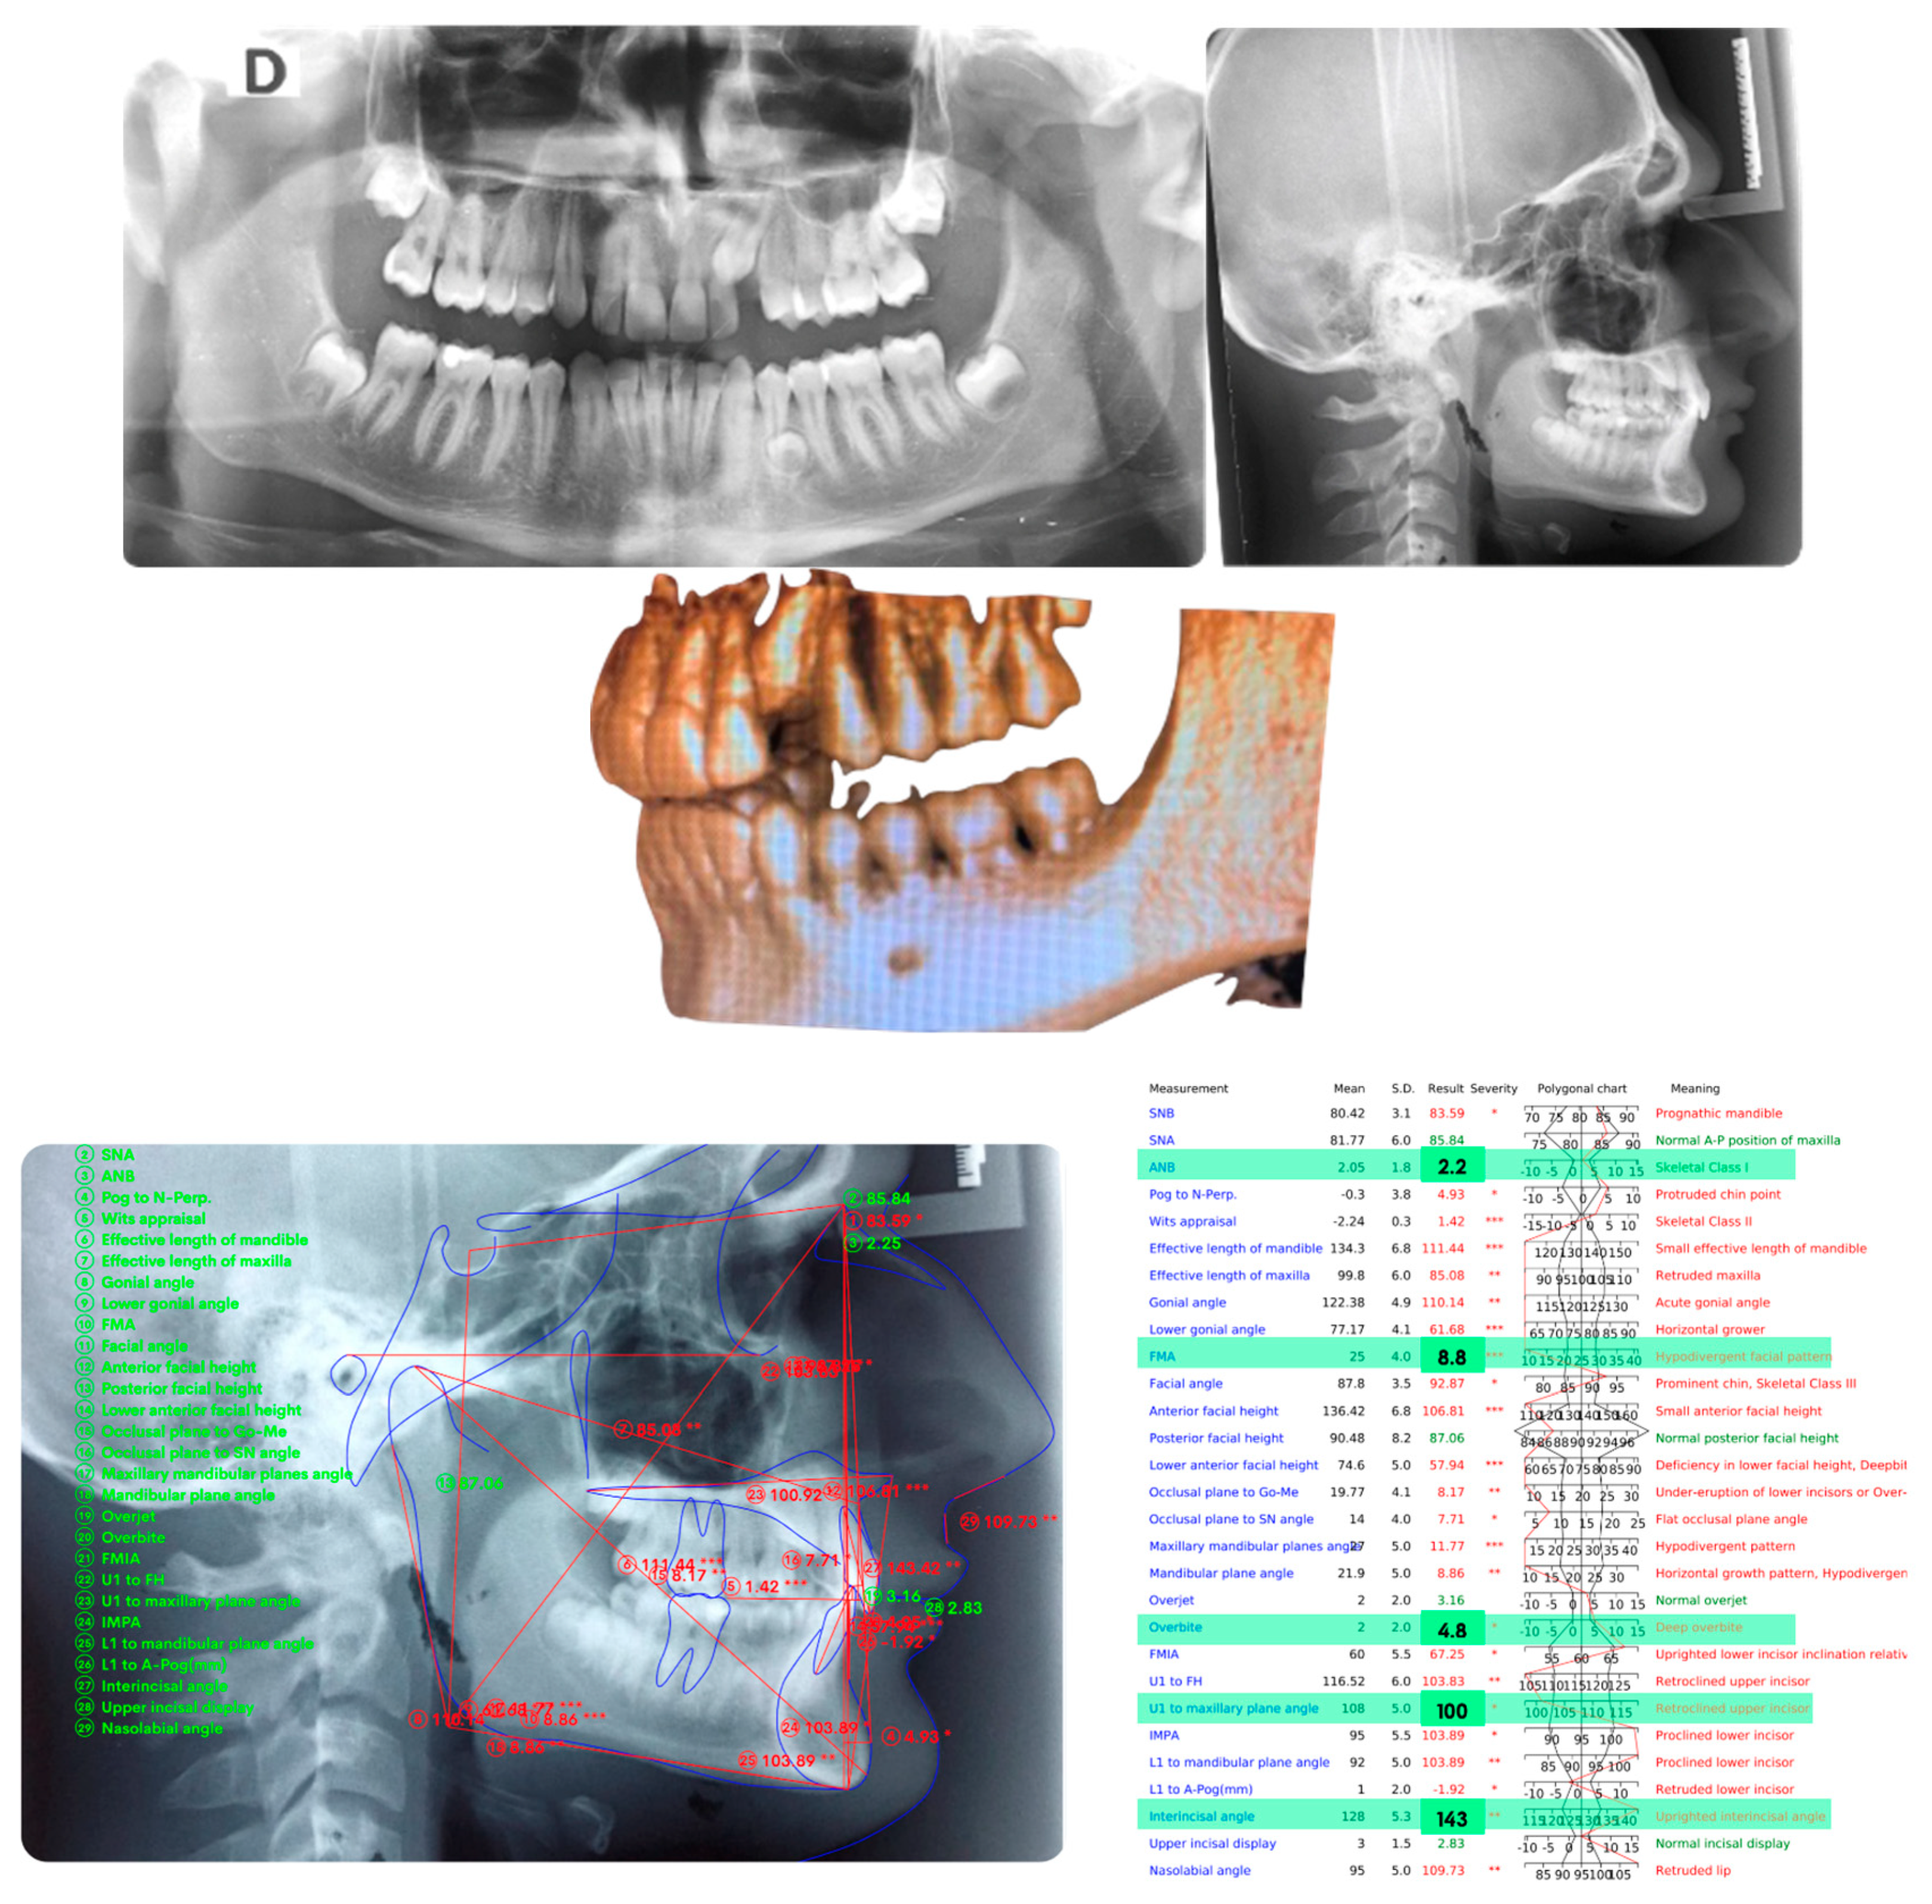

Figure 2 panoramic and CBCT showing the moderate palatal 2.3 impaction. Lateral X-rays confirming a Class I skeletal and dental malocclusion with deep bite.

Figure 2.

Cephalometric analysis, panoramic and CBCT of the first patient. Lateral X-rays confirming a Class I skeletal and dental malocclusion with deep bite.